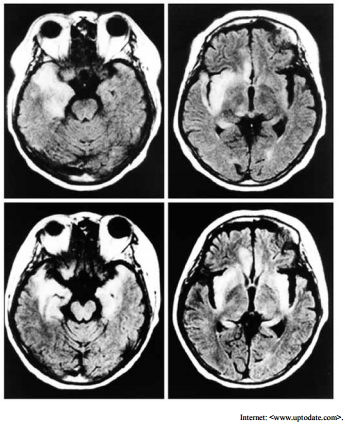

Um paciente com vinte e cinco anos de idade foi admitido em um hospital apresentando, havia cinco dias, febre persistente, cefaleia holocraniana, oscilações de humor e alterações no seu comportamento habitual. O paciente fez uso de analgésicos e antitérmicos, em casa, administrados pela própria família, mas a resposta aos medicamentos foi parcial e temporária. No quinto dia, o paciente estava excessivamente sonolento, e apresentou crise convulsiva tônico-clônica, sendo então levado para atendimento médico de urgência. Acerca desse caso clínico, julgue o item a seguir considerando o exame de imagem mostrado. Essa doença, embora seja de elevada morbidade e rápida evolução, acomete, em geral, pessoas imunocompetentes.

Um paciente com vinte e cinco anos de idade foi admitido em um hospital apresentando, havia cinco dias, febre persistente, cefaleia holocraniana, oscilações de humor e alterações no seu comportamento habitual. O paciente fez uso de analgésicos e antitérmicos, em casa, administrados pela própria família, mas a resposta aos medicamentos foi parcial e temporária. No quinto dia, o paciente estava excessivamente sonolento, e apresentou crise convulsiva tônico-clônica, sendo então levado para atendimento médico de urgência. Acerca desse caso clínico, julgue o item a seguir considerando o exame de imagem mostrado. Nessa doença, as alterações típicas do líquor incluem pleocitose linfocítica, aumento de proteínas e presença de eritrócitos, o que reflete a natureza hemorrágica dessa infecção.

Um paciente com vinte e cinco anos de idade foi admitido em um hospital apresentando, havia cinco dias, febre persistente, cefaleia holocraniana, oscilações de humor e alterações no seu comportamento habitual. O paciente fez uso de analgésicos e antitérmicos, em casa, administrados pela própria família, mas a resposta aos medicamentos foi parcial e temporária. No quinto dia, o paciente estava excessivamente sonolento, e apresentou crise convulsiva tônico-clônica, sendo então levado para atendimento médico de urgência. Acerca desse caso clínico, julgue o item a seguir considerando o exame de imagem mostrado. A cultura viral do líquor é o exame padrão-ouro para estabelecer o diagnóstico etiológico da doença no paciente em questão.

Um paciente com vinte e cinco anos de idade foi admitido em um hospital apresentando, havia cinco dias, febre persistente, cefaleia holocraniana, oscilações de humor e alterações no seu comportamento habitual. O paciente fez uso de analgésicos e antitérmicos, em casa, administrados pela própria família, mas a resposta aos medicamentos foi parcial e temporária. No quinto dia, o paciente estava excessivamente sonolento, e apresentou crise convulsiva tônico-clônica, sendo então levado para atendimento médico de urgência. Acerca desse caso clínico, julgue o item a seguir considerando o exame de imagem mostrado. O agente etiológico da infecção é do mesmo tipo que causa a meningite linfocítica recorrente, também conhecida com meningite recorrente de Mollaret.

Um paciente com vinte e cinco anos de idade foi admitido em um hospital apresentando, havia cinco dias, febre persistente, cefaleia holocraniana, oscilações de humor e alterações no seu comportamento habitual. O paciente fez uso de analgésicos e antitérmicos, em casa, administrados pela própria família, mas a resposta aos medicamentos foi parcial e temporária. No quinto dia, o paciente estava excessivamente sonolento, e apresentou crise convulsiva tônico-clônica, sendo então levado para atendimento médico de urgência. Acerca desse caso clínico, julgue o item a seguir considerando o exame de imagem mostrado. O tratamento do paciente em questão realiza-se à base de corticoide e anticonvulsivante. Em casos de presença de DNA viral no líquor, aplica-se aciclovir.